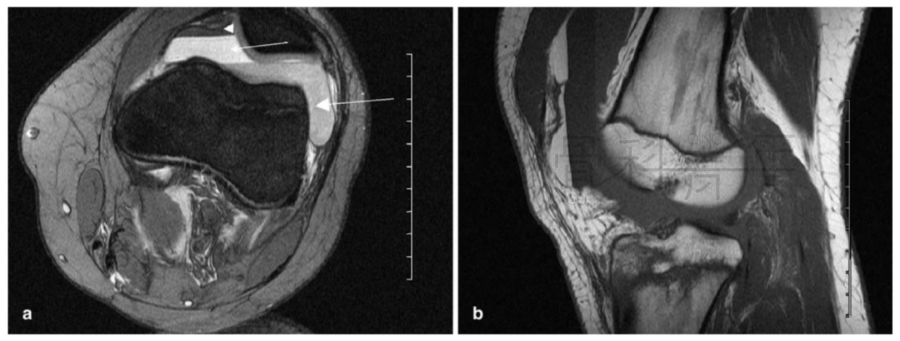

病例2 一例左膝外伤患者。在MR横断与矢状位上均可见明显液体分层(见箭头所示)。

病例3 在超声上和MR上,均可见明显液体分层。